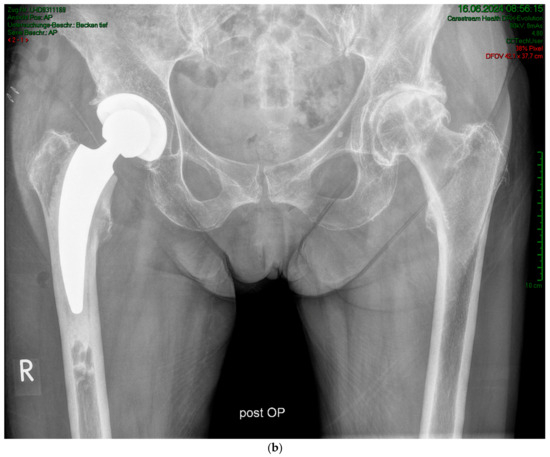

Case #1: Female patient, 81 years old, with osteoporotic bone, coxa vara, and a Dorr C femur. (a) Preoperative planning for a cemented A2 stem combined with a cementless ANA.NOVA Alpha Cup. The image shows good reconstruction of the leg length and offset. (b,c) Postoperative anteroposterior (b) and axial (c) radiographic imaging 1 week postoperatively. Correct position of the stem and complete cement mantle.

(a) Case #2: Osteoarthritis, female, 85 years old, bilateral sequential implantation of an A2 stem, Dorr B-C femora. (b) Left side: slight distalization of the cement stopper. (c) Right side: no positional change of the cement stopper during the operation.